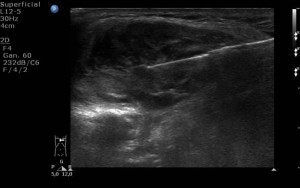

En este caso buscamos conocer la naturaleza benigna o maligna de la masa así como el tipo celular, por lo que lo adecuado para continuar con el diagnóstico es la BAG. Respecto a la forma de guiarla, al ser una lesión fácilmente accesible y bien localizable con ecografía, nos decantaremos por esta técnica, pues así evitamos irradiar al paciente de forma innecesaria.

Tras el estudio de la muestra por anatomía patológica el diagnóstico definitivo es linfoma B de células gigantes.

DIAGNOSTICO FINAL: LINFOMA B DE CELULAS GIGANTES